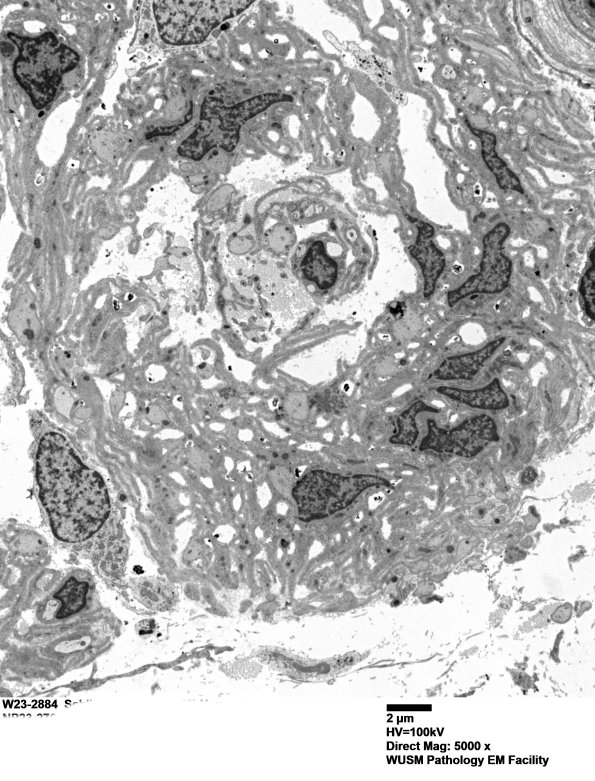

8C2A-C This is an even less structured POB that consists mostly of layered Schwann cell processes around a central area. (electron micrographs)